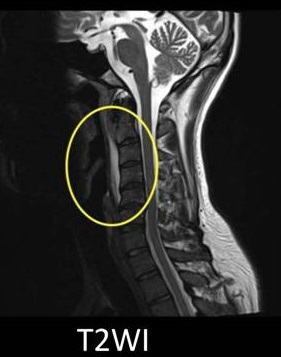

後縦靱帯骨化症(ossification of posterior longitudinal ligament:OPLL)とは、脊椎後縦靱帯が骨化し、脊髄と脊髄神経根を圧迫、感覚障害や運動障害を呈する病気です。後縦靱帯骨化症(OPLL)は男性に多く、その原因は不明ですが、遺伝的素因、性ホルモン異常、副甲状腺の病気やカルシウム・ビタミンDの代謝異常、糖尿病、肥満等が関与するとされます。

頚椎の後縦靱帯骨化症(OPLL)の症状は、

- 頚肩の凝り、痛み(後頸部痛)で首を回せない、体ごと振り向く

- 脊髄・脊髄神経根の圧迫による手足のシビレ、両手指の使いにくさ、麻痺、排尿障害(尿意があっても尿が出にくい)など

で、放置して悪化する事はあっても、改善する事はありません。

副甲状腺機能低下症では、大脳基底核の石灰化などの異所性石灰化(異所性骨化)が起こりますが、頚椎後縦靱帯骨化症(OPLL)などの脊柱靱帯骨化症の発症にも関与すると考えられます。(日骨代謝会誌 1986;3(3〜4):151-160)